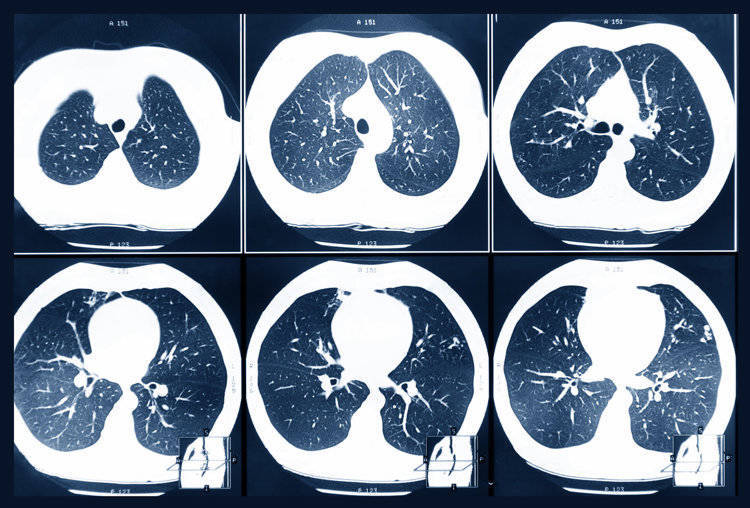

肺癌常见的有肺腺癌和肺鳞癌,无症状的肺癌多见于肺腺癌,一般肺腺癌会发生在支气管、肺泡上皮细胞上,因发生的位置在肺外周,是以也成为周围型肺癌。一些肺腺癌具有惰性滋长的特征,尤其是磨玻璃要素的,是以早期症状会更为不赫然。

1、抓续性增大/直径≥8mm的肺结节

肺结节是当代东说念主身上的常见问题,但淌若肺结节抓续变大,随访3~6个月发现结节增大≥2mm,一定要高度警惕可能是恶性的。还有就是查出直径≥8mm的肺结节,也可能是恶性的,概率为5~10%。

2、磨玻璃结节/密度

纯磨玻璃结节一般恶性的过程会低一些,淌若是搀杂磨玻璃结节的话,则恶性过程会赫然高涨。但也要聚蚁合节的大小来进行判断,即等于纯磨玻璃结节,体积≥10mm,恶性过程也很高。

3、分叶状/毛刺征/胸膜凹下征

分叶状是指结节边际不光滑,是由于肿瘤向各主义滋长不均匀所致。一朝发现结节有赫然的分叶,恶性过程会赫然增多;

毛刺征则是指结节边际呈细线状/毛刷状以辐照状漫步,这是由于肿瘤组织浸润周围组织滋长所致,也可能是肿瘤周围的炎性响应导致的纤维化,一般是恶性肿瘤的征兆;

胸膜凹下征是结节和胸膜之间有赫然的三角形、幕状影像,多在肺癌患者身上出现。